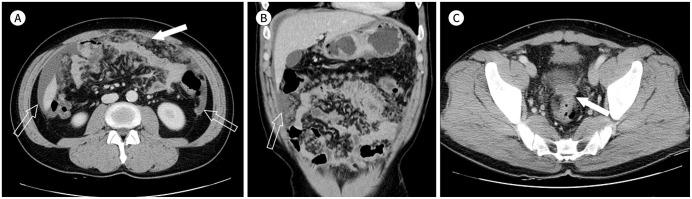

Although primary tumors in the mesentery and omentum are relatively rare, it is often necessary to distinguish them from other non-tumorous diseases. Since the omentum and mesentery are major routes for the spread of various abdominal diseases, the anatomy, type, and pattern of the diseases affecting these organs should be known in detail for accurate differential diagnosis. In addition, it is important to detect and promptly treat hidden lesions in the mesentery and omentum. Therefore, careful observation of the area where the lesion occur should be emphasized when assessing mesentery and omentum in abdominal CT.

尽管肠系膜和网膜的原发性肿瘤相对少见,但常常需要将它们与其他非肿瘤性疾病区分开来。由于网膜和肠系膜是各种腹部疾病的主要传播途径,为了进行准确的鉴别诊断,应详细了解影响这些器官的疾病的解剖结构、类型和模式。此外,检测并及时治疗肠系膜和网膜中的隐匿性病变也很重要。因此,在腹部CT评估肠系膜和网膜时,应强调仔细观察病变发生的区域。